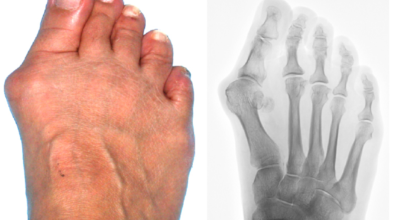

엄지발가락이 두 번째 발가락 쪽으로 과도하게 휘고, 엄지발가락과 연결되는 중족골이 반대로 안쪽으로 기울어지며 발가락이 발등 쪽으로 휘거나 회전(엄지발가락 축을 중심으로 내측으로 회전; 회내)하는 삼차원적인 변형을 말합니다.

무지외반증이 심해지면 엄지발가락이 두 번째 발가락과 겹치거나 관절이 탈구되어 전반적으로 발을 디디기 어려운 상태가 될 수 있습니다. 건강보험심사평가원의 무지외반증 환자 통계에 따르면, 40대 이상에서 가장 많이 발생하며, 여성 환자 비율이 남성보다 월등히 높다고 합니다.

육안으로 확연히 엄지발가락의 변형이 보이며, 초기에는 굳은살이 생기고 약간의 통증도 동반됩니다. 엄지발가락의 돌출 부위에 통증이 발생하는데, 이 부위가 신발에 자극을 받아 두꺼워지고 염증이 생겨 통증이 유발됩니다. 발바닥에 굳은살이 생기면 정상적인 보행이 어려워지고, 심한 경우에는 통증 때문에 신발 착용이나 정상적인 보행도 힘들어질 수 있습니다. 증상이 지속적으로 악화되면 엄지발가락이 겹치거나 탈구될 수도 있습니다.

엄지발가락이 옆으로 휘어져 관절에 비정상적인 힘이 가해지면 퇴행성 관절염이 생길 수 있습니다. 또한, 엄지발가락이 발바닥의 압력을 2, 3번째 발가락으로 옮기면서 발바닥에 굳은살이 발생할 수 있고, 발가락 뼈 사이의 신경이 붓고 통증을 유발하는 지간신경종이 합병될 수 있습니다.